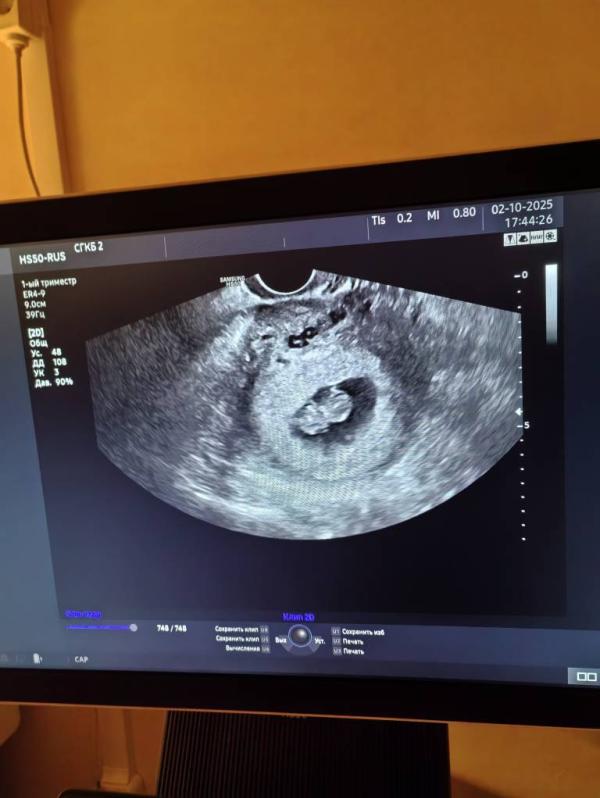

Сходила на узи сегодня, прослушали сердцебиение , плацента по задней стенке формируется, все хорошо ) 8 числа пойду сдавать анализы и вставать на учёт ) уже скоро и на скрининг первый запишут )

Спасибо большое) у меня значка не видно разве? 🤔 8 недель срок ) ну можно сказать что 9 уже